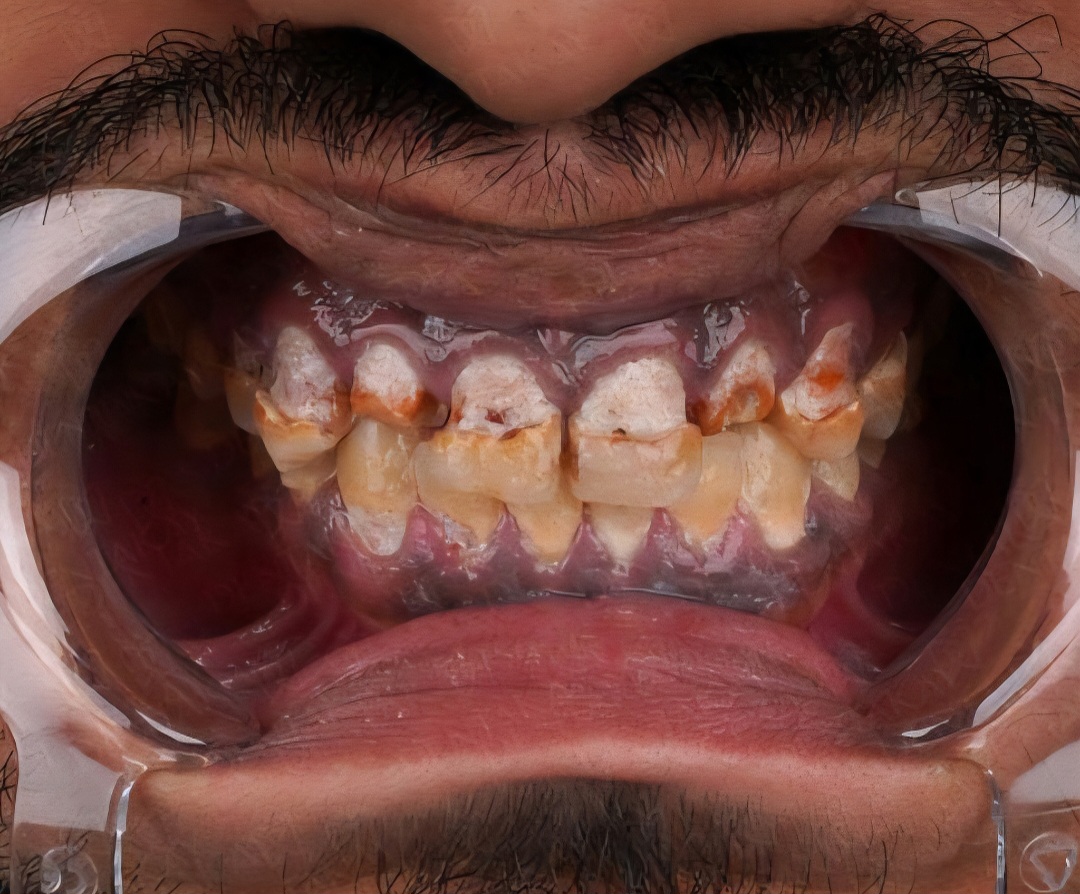

۱. دندانپزشکی زیبایی

لمینت سرامیکی در لابراتوار ساخته شده و مقاومت و دوام بالاتری دارد در حالی که کامپوزیت ونیر مستقیم روی دندان در مطب شکل داده میشود. لمینت هزینه بیشتری دارد اما ماندگاری بالاتری (۱۰-۱۵) سال نسبت به کامپوزیت (۷۵) سال) دارد.

کامپوزیت ونیر پیشرفته:

🔹️ استفاده از مواد نانوکامپوزیت با مقاومت بالا

🔹️ تکنیک لایهگذاری (Layering Technique) برای طبیعیتر شدن نتیجه

🔹️ پولیش حرفهای برای درخشندگی طولانیمدت